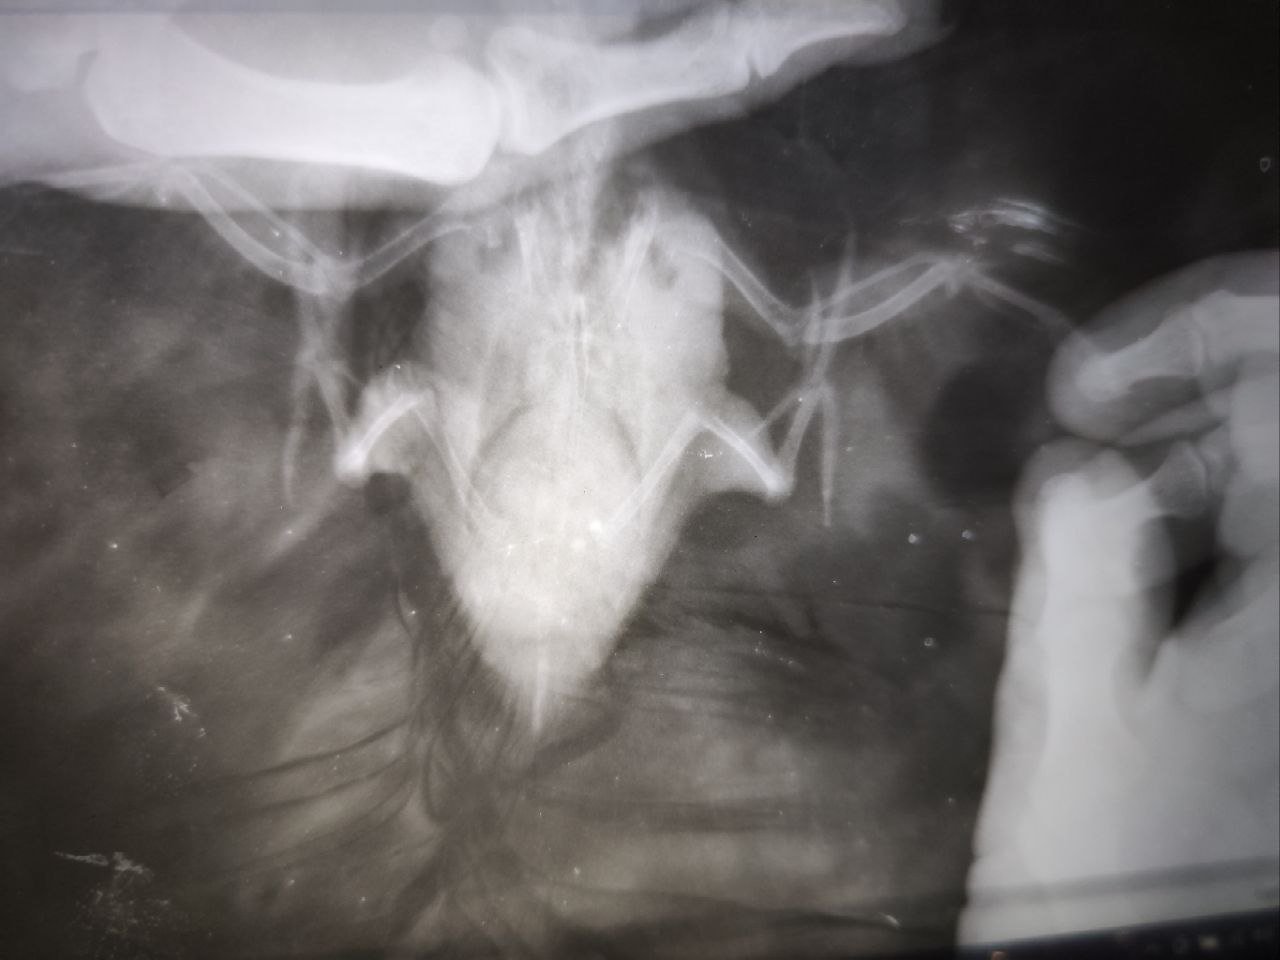

по анализу- слабо выраженная недостаточность поджелудочной.

По рентгену- максимум что смогла выжать из снимка покажу ниже.

Семенников не видно как органа.

Практически вся целомическая полость занята образованием, не имеющим очерченной поверхности (возможно не одним).

Велика вероятность н/о семенников, возможно вторичным , а первичное- печень.

степан 2.png